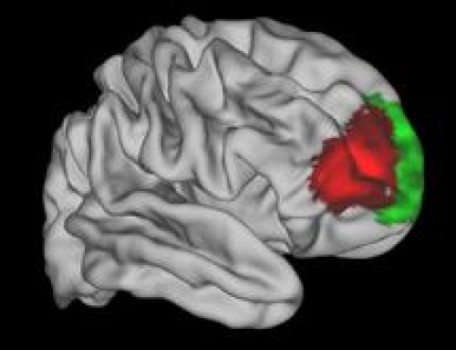

La zona roja parece exclusiva de los humanos. Fuente: Universidad de Oxford.

Los investigadores fueron capaces de comparar las 12 áreas de esa región del cerebro humano con la organización de la corteza prefrontal de mono. En general, eran muy similares, dado que 11 de las 12 áreas se encuentran en ambas especies y están conectadas a otras áreas del cerebro de maneras muy similares.

Sin embargo, un área de la corteza frontal ventrolateral humana no tiene equivalente en el macaco. El autor principal del artículo, Franz- Xaver Neubert, de la Universidad de Oxford, añade: "Esta zona ha sido identificada con la planificación estratégica y la toma de decisiones, así como con la "multi-tarea".

Los investigadores fueron capaces de comparar las 12 áreas de esa región del cerebro humano con la organización de la corteza prefrontal de mono. En general, eran muy similares, dado que 11 de las 12 áreas se encuentran en ambas especies y están conectadas a otras áreas del cerebro de maneras muy similares.

Sin embargo, un área de la corteza frontal ventrolateral humana no tiene equivalente en el macaco. El autor principal del artículo, Franz- Xaver Neubert, de la Universidad de Oxford, añade: "Esta zona ha sido identificada con la planificación estratégica y la toma de decisiones, así como con la "multi-tarea".